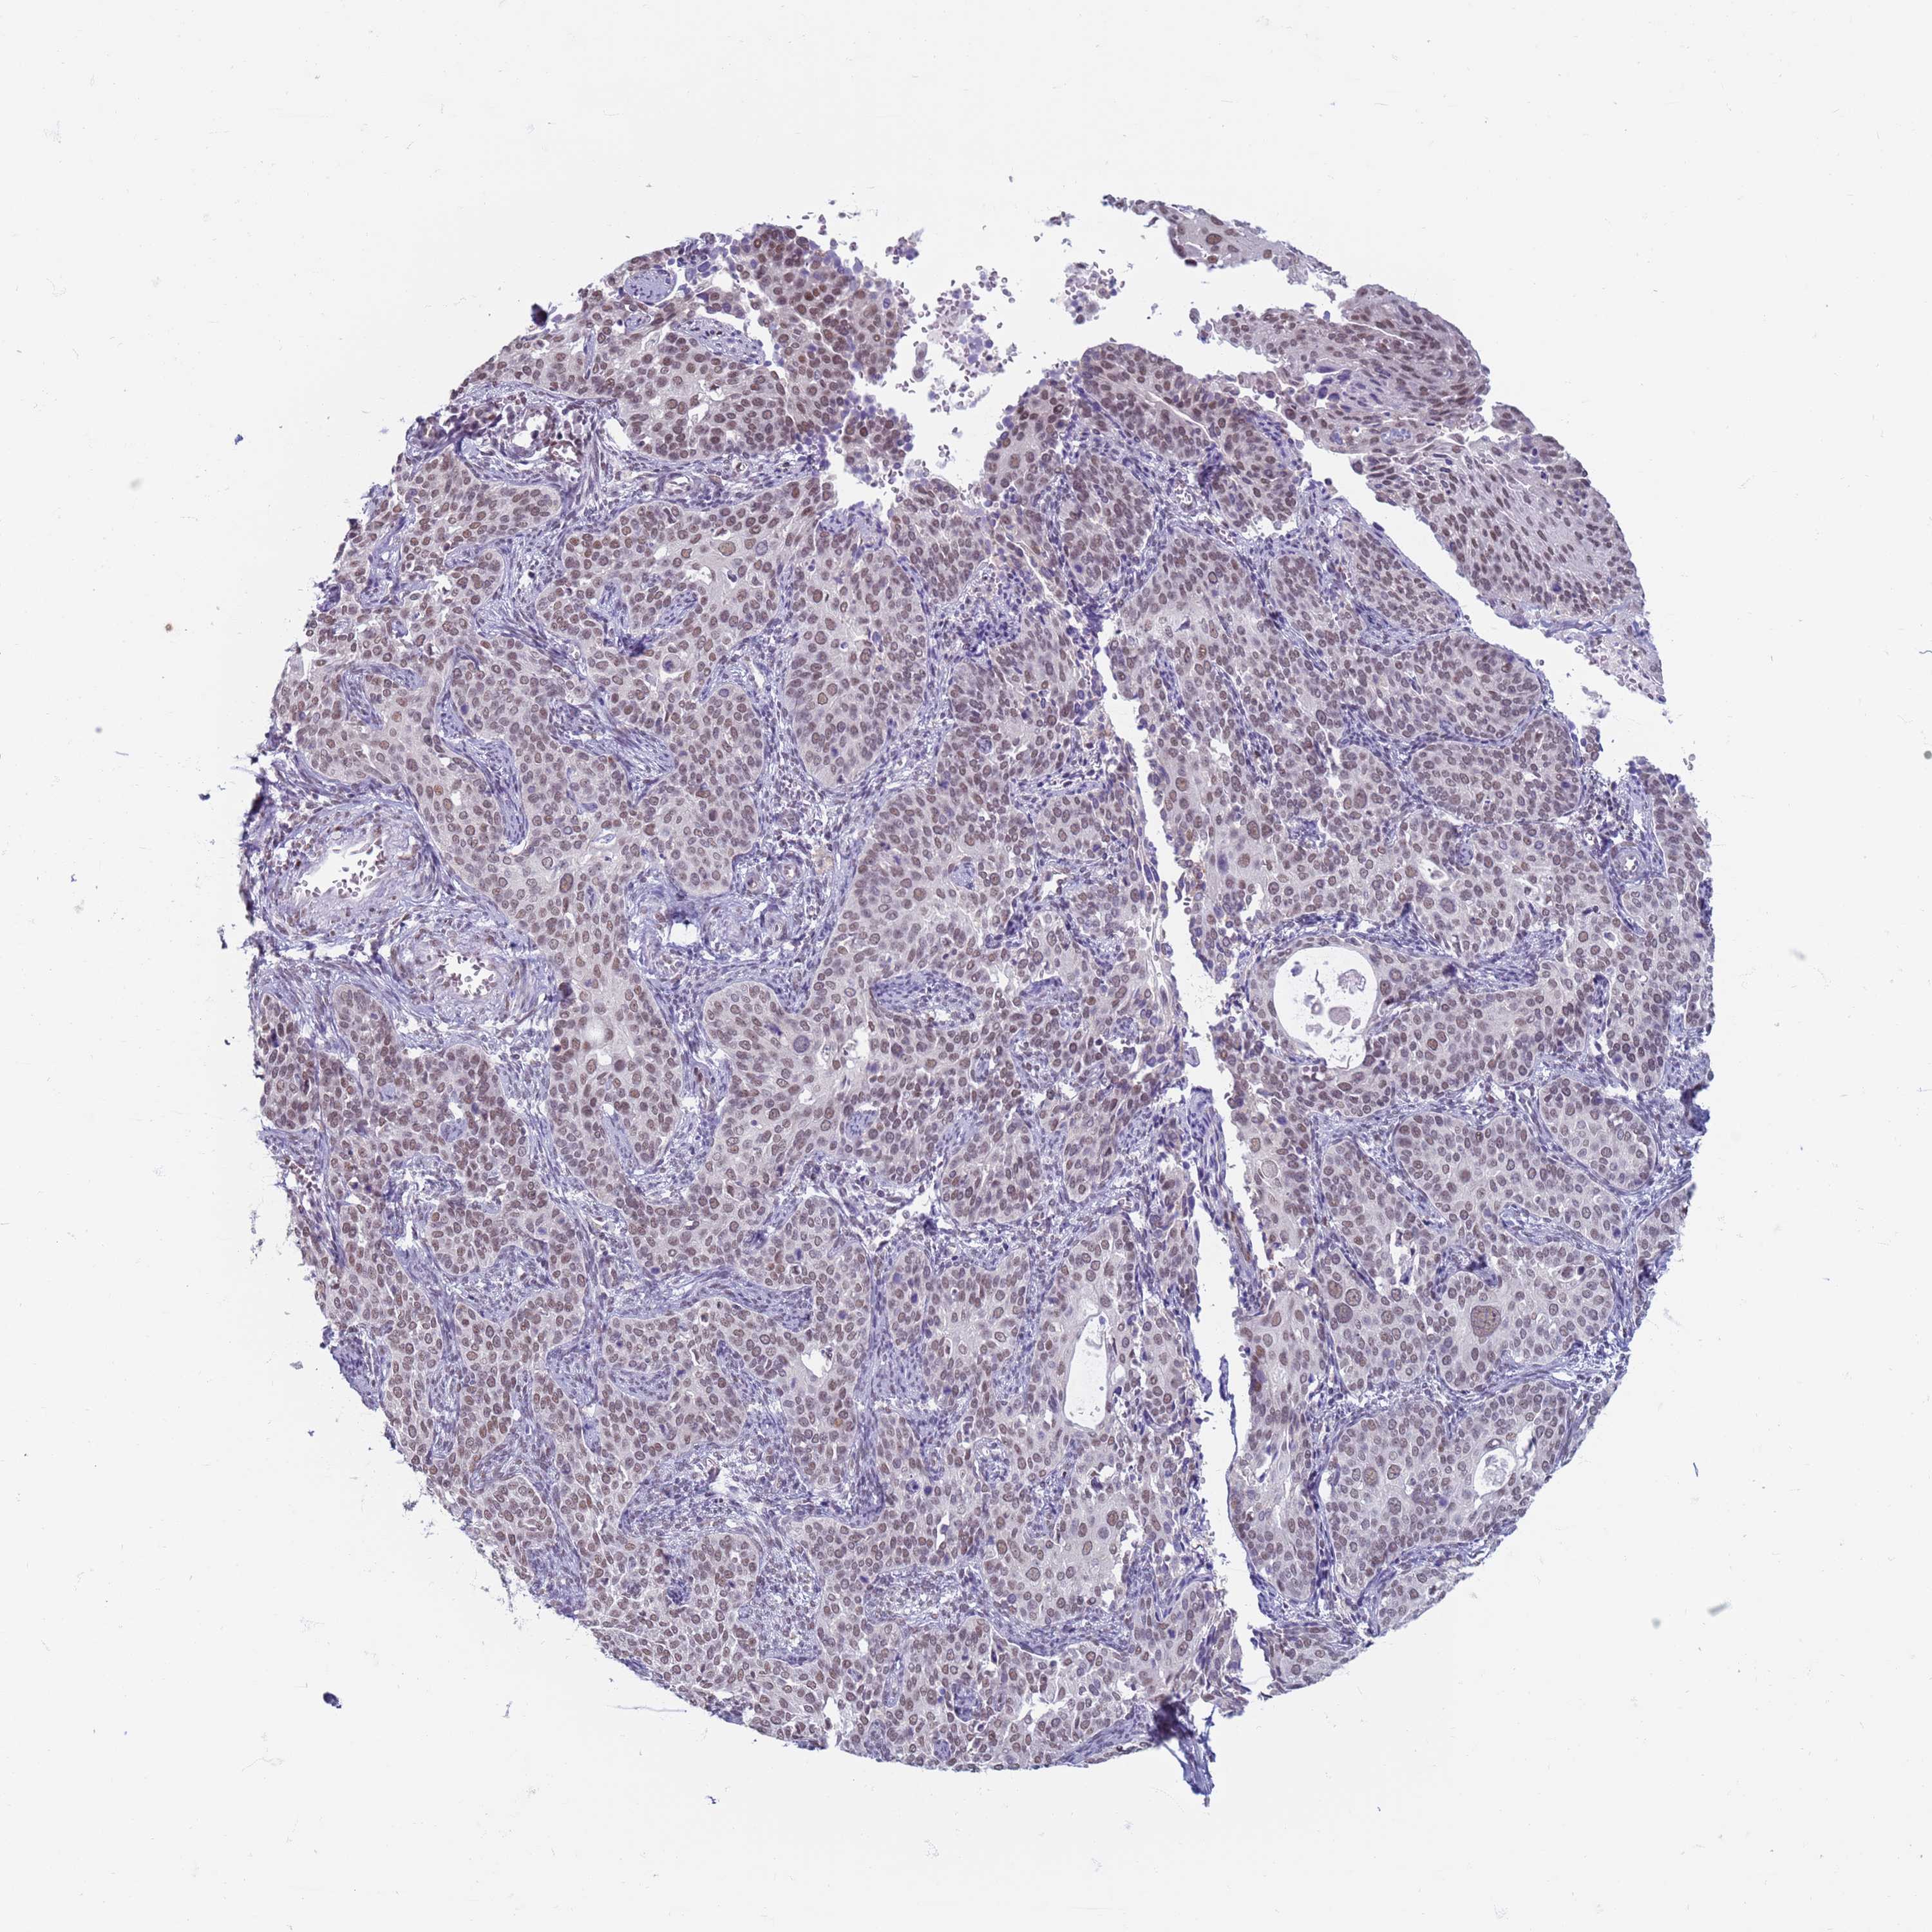

CERVICAL CANCER - Protein expressioni

A mouse-over function shows sample information and annotation data. Click on an image to view it in a full screen mode. Samples can be filtered based on level of antibody staining by selecting one or several of the following categories: high, medium, low and not detected. The assay and annotation is described here.

Note that samples used for immunohistochemistry by the Human Protein Atlas do not correspond to samples in the TCGA dataset.

Antibody stainingi

Antibody staining in the annotated cell types in the current human tissue is reported as not detected, low, medium, or high, based on conventional immunohistochemistry profiling in selected tissues. This score is based on the combination of the staining intensity and fraction of stained cells.

Each image is clickable and will lead to virtual microscopy that enables deeper exploration of all samples and also displays staining intensity scores, fraction scores and subcellular localization as well as patient and tissue information for each sample.

Antibody HPA041906

Antibody HPA043552

Staining

High

Medium

Low

Not detected

Intensity

Strong

Moderate

Weak

Negative

Quantity

>75%

75%-25%

<25%

None

Location

Nuclear

Cytoplasmic/membranous

Cytoplasmic/membranous,nuclear

Squamous cell carcinoma, NOS

Adenocarcinoma, NOS